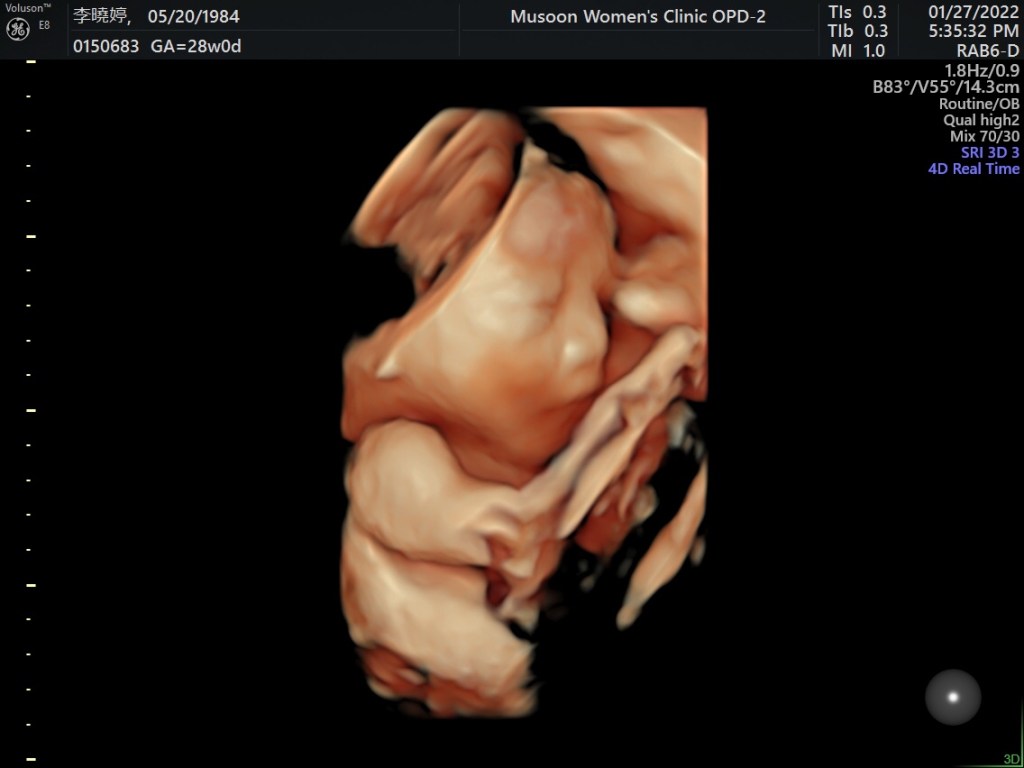

托著9個月大的肚子,行動更是不方便,盆底肌拉扯、骨盆等關節翻身都會出現驚人的“咖一聲”,這輩子還沒聽過恥骨聯合週圍的關節會咖一聲,這也是我唯一痛苦來源。

雖然身體再怎麼不適,但內心感到幸福的,或許知道這是最後一次懷孕,格外珍惜與寶寶同為一體的時間。身為女人擁有懷孕這麼特別的體驗,真的很開心也很幸運的可以體會這件事,感謝我的身體、子宮,還有精神、心靈,短短2年支撐我孕育兩胎的計劃,非常不容易,能撐到同一個時間生產,我都佩服自己了,中間還滑倒劈腿、不斷的顧9公斤的吳藍天而受傷N次,精神上、心靈上承受的壓力,在這疫情期間,每個懷孕的媽媽都承受很大的壓力。